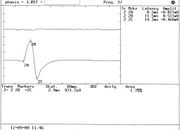

| 13:33, 18 August 2023 | Jaw jerk in capsaicinica.bmp.png (file) |  |

77 KB | Gianni | 1 | |